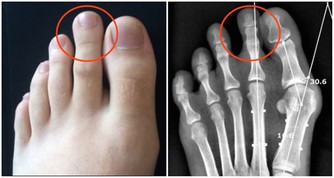

3、水腫腎臟是人體代謝水的器官,腎不好,水就會蓄積。

有的人早上起來發現眼皮浮腫,或者雙腳、雙腿浮腫,都要考慮腎臟的問題。

5、尿液混濁有泡沫現在是夏季,又到了喝水的季節,因為大量的汗液排除,所以喝水成為了最簡單而方便的解暑方式。而喝的水中海油一部分會通過尿液排除,所以尿液的清澈與否以及泡沫的多少都是很直觀的判斷腎臟的健康狀況。而腎臟一旦出現問題,就會與腎炎、腎結石、腎功能衰竭等疾病直接相關,嚴重的甚至會威脅生命。若小便泡沫突然變多,長時間不消失,說明尿液中排泄的蛋白質較多,尿液顏色異常,呈濃茶色、醬油色或混濁如洗米水時。都應引起重視,這些都說明你的腎臟出現了問題。6、早起身體會出現浮腫我們每天都需要喝大量的水來滿足身體的需要,因為身體的新陳代謝都需要水的參與,而這麼多的水到身體中都會經過哪裡呢?腎臟是人體代謝水分的器官,腎臟好的人,整個人的泌尿系統也會很健康的循環,腎不好,水就會蓄積,尤其是在早上很容易出現浮腫的現象。例如:我們晚上要是大量的喝水,就會加重腎臟的負擔,第二天容易在眼睛周圍出現水腫的癥狀。所以我們正常的飲水的情況下,如果還會經常出現早起眼皮浮腫,或者腳、腿的浮腫,都說明你的腎臟可能出現了問題了。